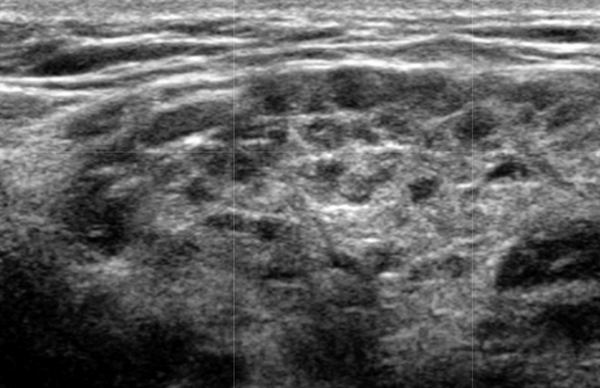

- Повышенная паренхиматозная васкуляризация при СШ на ультразвуковом сканировании с ЦДК

Серошкальное УЗИ. Вовлеченность может казаться асимметричной. Ранние стадии «милиарных» кист (точечные кистозные изменения ≤ 1 мм) могут быть пропущены, однако их легко увидеть на УЗИ на более поздних стадиях. Диффузная железистая гипоэхогенность может быть только признаком раннего синдрома Шегрена, как и неоднородная паренхиматозная эхоструктура. Множественные дискретные гипоэхогенные очаги, разбросанные по слезным и слюнным железам. Солидные очаг представляют собой агрегаты лимфоцитов. Микроцисты возникают из-за деструкции ацинусов или расширения терминального протока из-за сжатия лимфоидными агрегатами. Макроцисты образуются из-за разрушения слюнной ткани. Гиперэхогенные полосы (фиброз) и кальцификаты обычно связанны с хроническим заболеванием. Система балльной оценки УЗИ (основанная на суммировании баллов по эхогенности паренхимы, однородности, наличию гипоэхогенных участков, гиперэхогенных отражений и четкости границ слюнных желез) хорошо коррелирует с результатами биопсии околоушной железы. Лимфоматозное изменение проявляется в виде доминирующего, нечеткого, твердого, гипоэхогенного образования в слюнных железах ± поражение лимфатических узлов.

Цветной допплер. Повышенная паренхиматозная васкуляризация при синдроме Шегрена и коррелирует с тяжестью заболевания

4. УЗИ околоушной железы при синдроме Шегрена:

• На ранних стадиях точечные изменения (кисты менее 1 мм) можно пропустить, но на поздних стадиях нарушения очевидны

• Повышение интенсивности кровотока при допплеровском исследовании

Что покажет УЗИ слюнных желез при болезни Шегрена

- Фиброзные изменения паренхимы

- Уменьшение эхогенности.